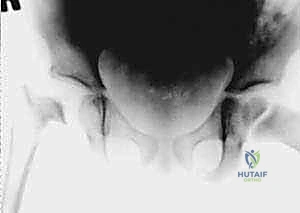

- الموجات فوق الصوتية (Ultrasound): هي الأداة الذهبية والأسرع لتأكيد وجود ارتشاح أو تجمع سوائل (Effusion) داخل كبسولة مفصل الفخذ. يمكن إجراؤها في العيادة أو الطوارئ فوراً.

- الأشعة السينية (X-rays): تُجرى لاستبعاد وجود كسور أو أورام. في الأيام الأولى للالتهاب القيحي، قد تظهر الأشعة طبيعية، أو قد تظهر اتساعاً في المسافة المفصلية بسبب تجمع الصديد، أو خلعاً جزئياً لرأس الفخذ. التغيرات العظمية المدمرة لا تظهر إلا في مراحل متأخرة (وهو ما نسعى لتجنبه).

4. بزل المفصل (Arthrocentesis) - المعيار الذهبي

إذا أكدت الموجات فوق الصوتية وجود سائل، وكانت الأعراض السريرية والمخبرية تشير إلى التهاب قيحي، فإن الخطوة الحاسمة هي سحب عينة من هذا السائل (تحت توجيه السونار وبمخدر موضعي أو عام).